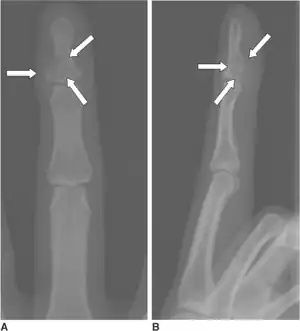

Calcifying aponeurotic fibroma-a,b)Show eccentrically located osteolytic lesion at base of distal phalanx